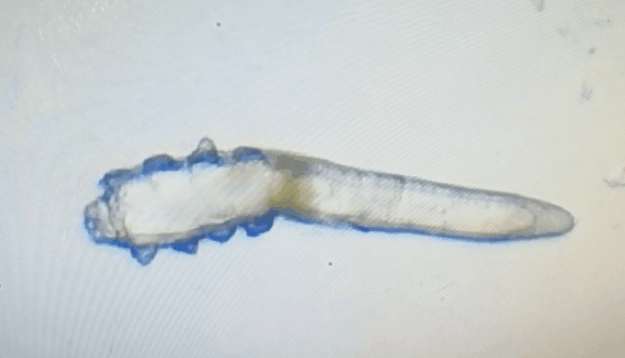

廈門(mén)眼科中心眼表及角膜病專家商旭敏博士指出:蠕形螨中的毛囊蠕形螨和皮脂蠕形螨可寄居于人體。在眼部,毛囊蠕形螨常寄居于睫毛囊,而皮脂蠕形螨多寄居于眼瞼皮膚的皮脂腺和瞼板腺。蠕形螨瞼緣炎是蠕形螨感染瞼緣所致的慢性炎性反應(yīng)性疾病,主要累及瞼緣皮膚、睫毛囊和腺體以及瞼板腺,以眼癢、眼異物感、眼干、瞼緣充血、鱗屑及睫毛根部袖套狀分泌物等為典型臨床表現(xiàn),嚴(yán)重者可引起結(jié)膜及角膜并發(fā)癥,該病可能具有一定的傳染性。

蠕形螨的危害不容小覷?。?!

蠕形螨會(huì)引起睫毛異常,引發(fā)瞼緣炎性反應(yīng),瞼板腺堵塞,引起結(jié)膜炎、角膜炎等并發(fā)癥,嚴(yán)重的話將發(fā)生角膜穿孔致視力損傷甚至失明。